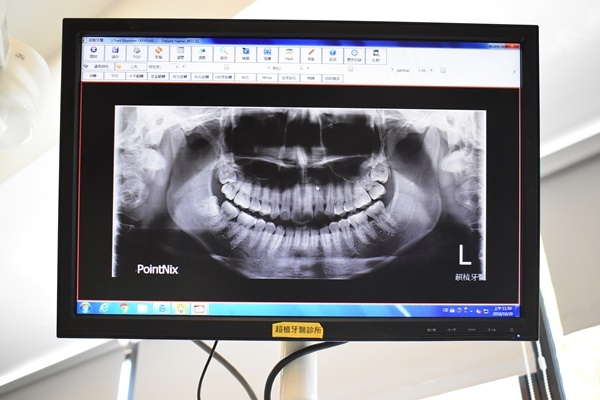

趁著今年尾牙抽到大紅包,想著與其存著不花不如好好犒賞自己,就這樣我再度來到台中北區超植牙醫找陳奕安醫師要他替我植牙,在做植牙前其實我也做了一番功課,因為住在台中北區,所以就是以我去過的超植牙醫為中心向外延伸到其他也在北區的牙醫,我每一間牙醫我都過去詢問植牙的價格以及詳細的治療內容,植牙價格是不是有包含哪些項目等...問到後來其他牙醫都覺得我是來找碴的,但我只是想選cp值比較高的牙醫啊...

緊接著就開始上麻藥昏昏睡去...再醒來陳奕安醫師已經把牙體植入口腔了,接下來就是等傷口復原再裝上新的牙齒,但那也是幾個月後的事了~